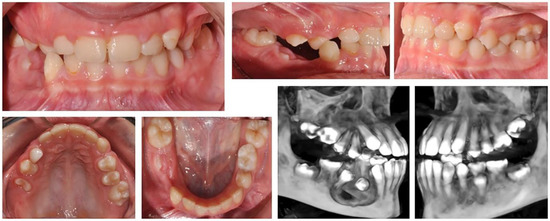

2.2.2. Clinical Case 2–Impaction of Upper-Right First Molar

The second case involved a 10-year-old girl sent for orthodontic treatment by a maxillofacial surgeon. A cystic lesion involving teeth 44 and 45 was detected, operated on and tooth 44 was extracted. A follicle cyst was detected in the upper dental arch around tooth 16, which changed the direction of development of the germ of the upper-right first molar (Figure 3). The molar was impacted with the crown in vestibular direction. Its orthodontic traction was recommended. For this, it was necessary to construct an anchorage area in the palate. The characteristics of the bone did not allow for the use of mini-implants. Therefore, the plan involved a PDaA, which included the premolars on both sides and the left first molar, as well as part of the hard palate. In the second clinical case, a wider palatal part was used, which engaged the hard palate in the support system. The purpose of this solution is the maximum support for rotational and extrusive movement of the upper-right first molar. During treatment, the patient suffered trauma, and the alveolar bone in the upper-central incisors was fractured. The stable distal segment was a good decision in this case. In the area of tooth 16, a “ladder” was designed with a series of hooks for attaching the elastic chain. The grid was printed from Co-Cr metal.

Figure 3. Oral status and CBCT examination of a patient with cystic lesions in the upper and lower jaw. Upper-right first molar was impacted with changed direction of crown position.